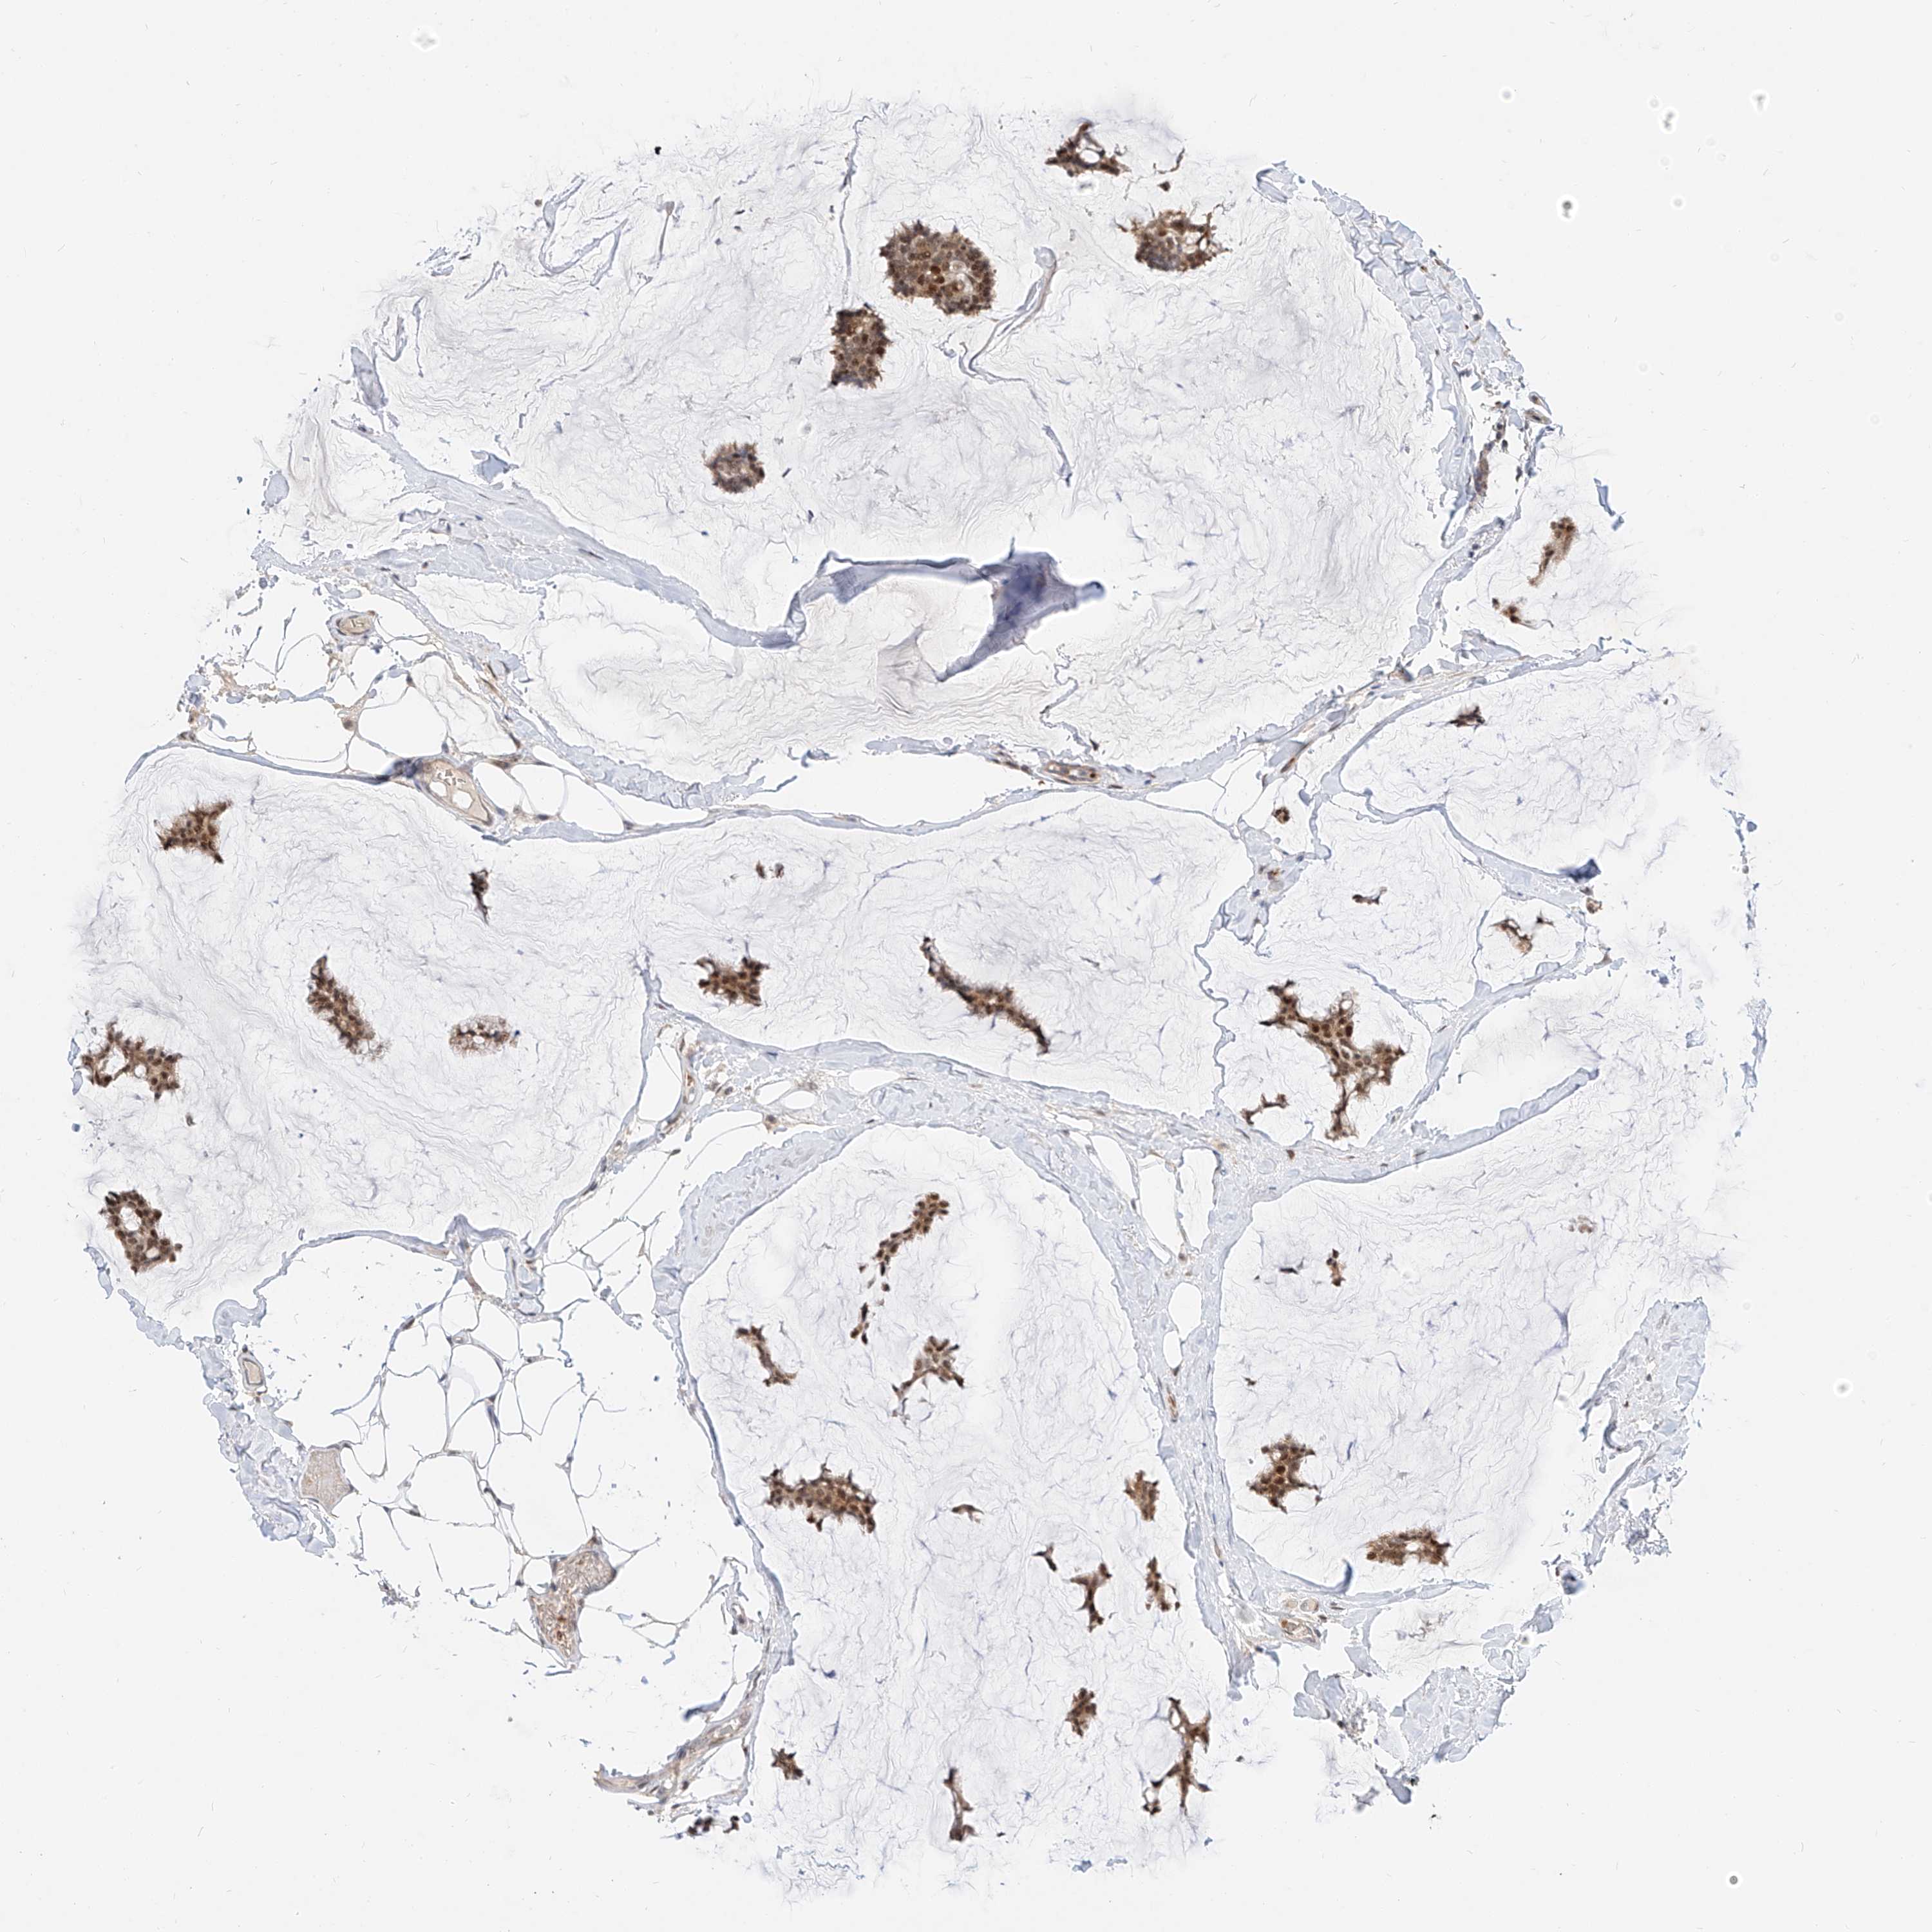

BRCA TCGA BRCA VALIDATION PROTEIN EXPRESSION

ANTIBODIES

AND

VALIDATION